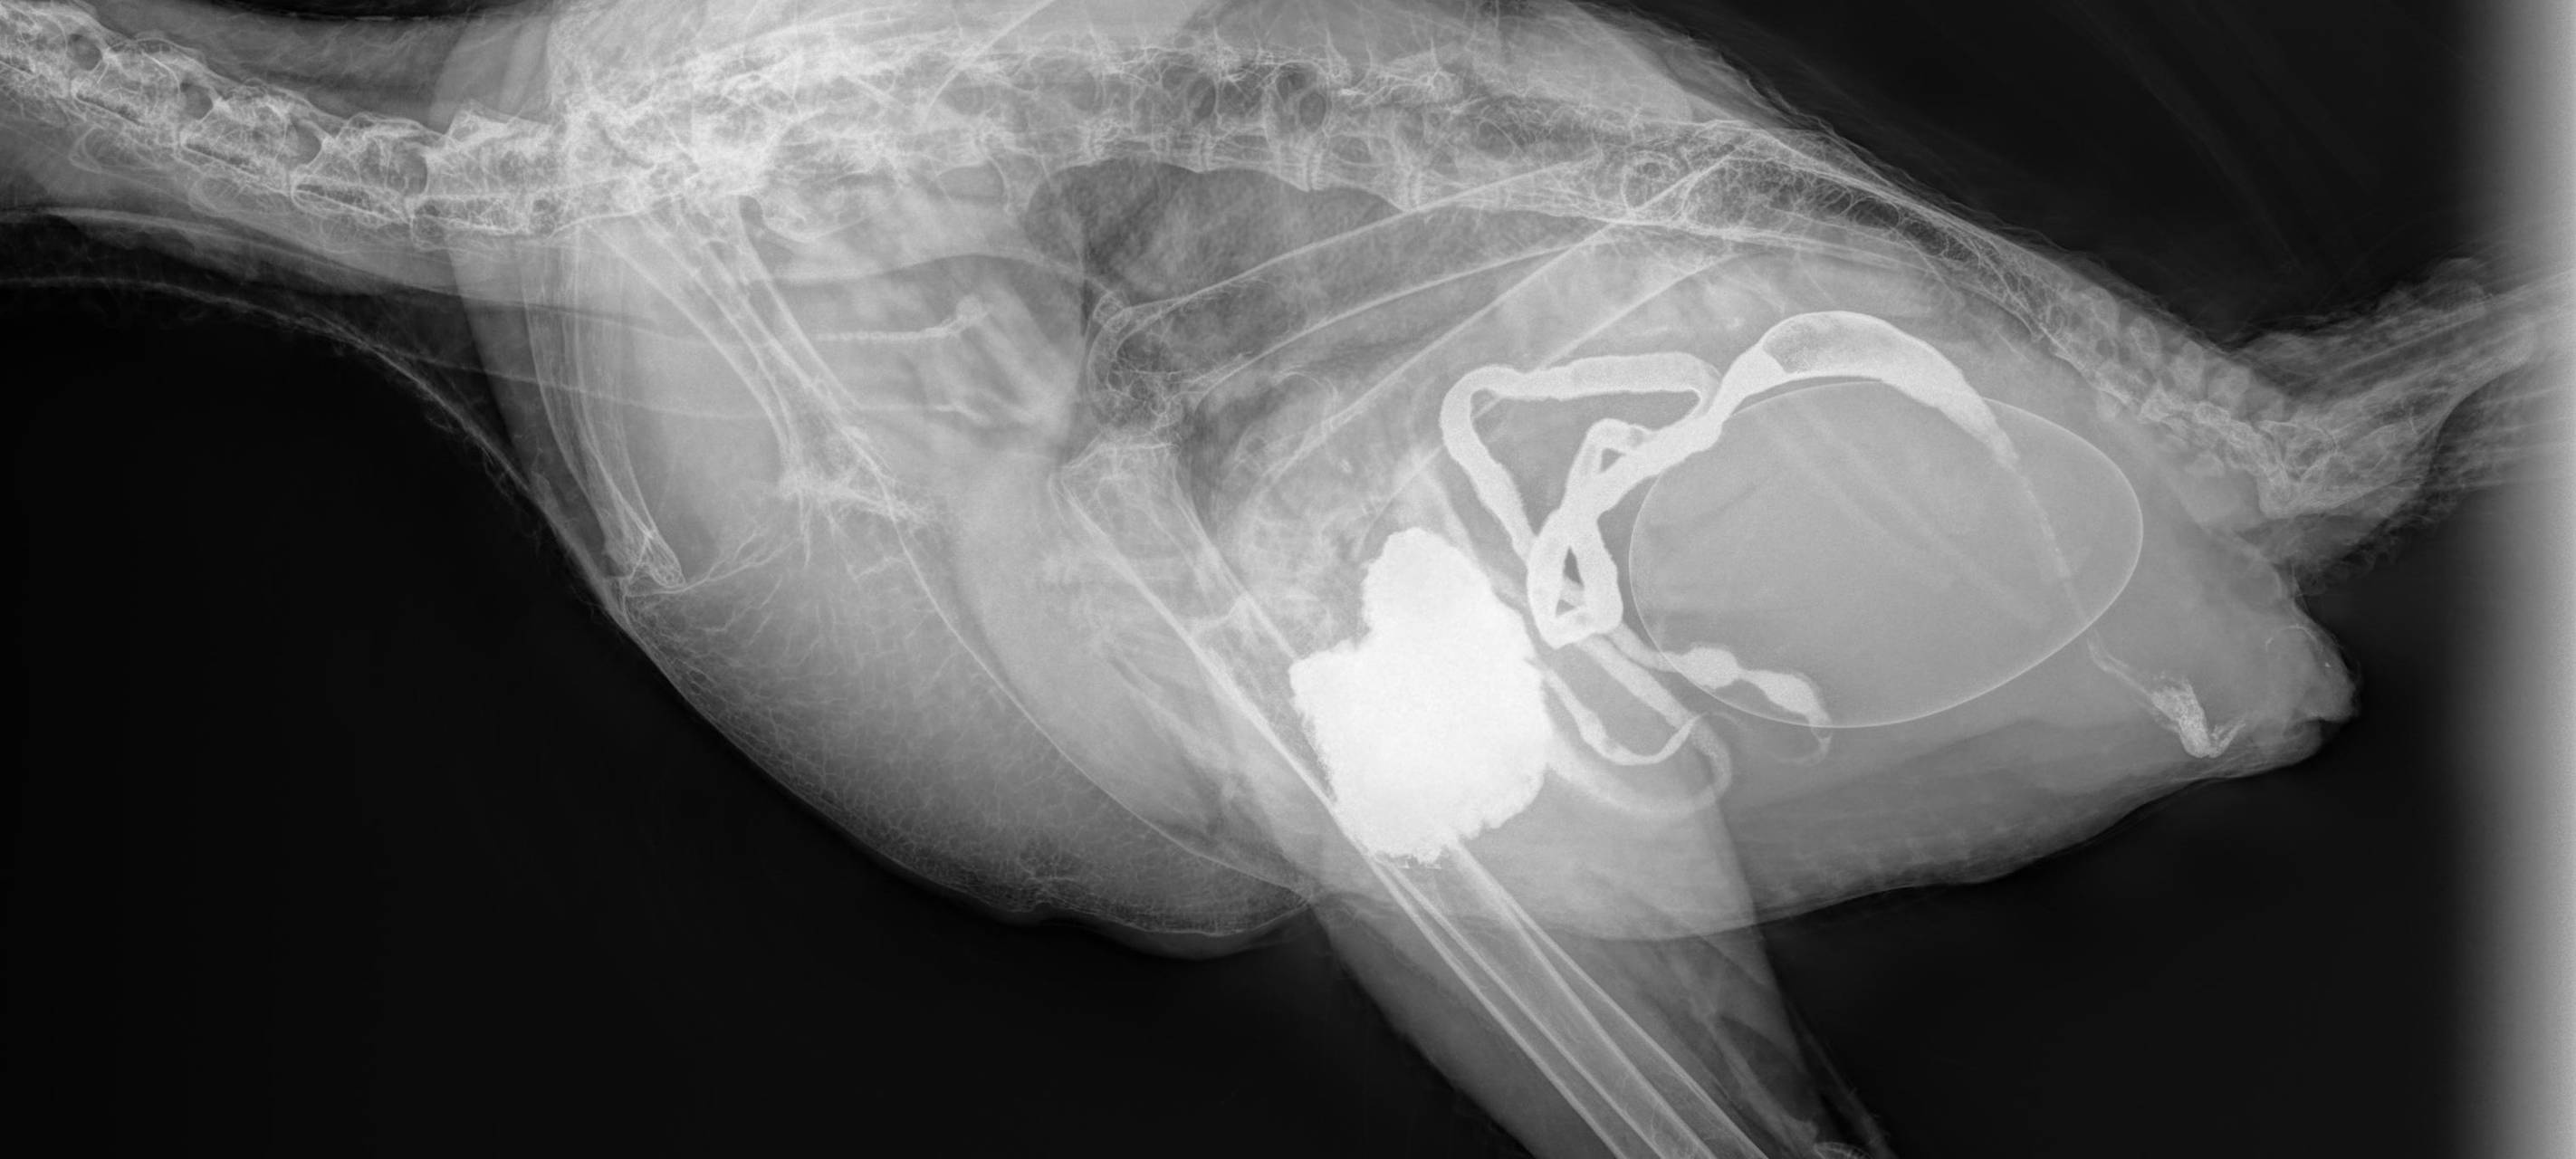

Der Zoo Duisburg hat ein neues Röntgengerät und damit konnten die Tierärztinnen im Zoo Duisburg innerhalb von nur zwei Sekunden feststellen, dass die Baumratte sich nix gebrochen hat und dass bei Hornrabe Margot ein Ei festgesessen hat. Das neue Röntgengerät ist digital, schickt die gestochen scharfen Bilder sekundenschnell direkt auf ein Laptop und das Allerbeste: Es ist mobil. Die Ärztinnen können also mit dem Gerät ins Gehege und die Tiere schnell röntgen, ohne diese allzu sehr zu stressen.